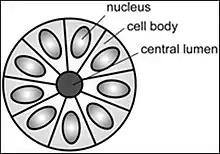

Structure of a Flexner–Wintersteiner rosette

Structure of a Flexner–Wintersteiner rosette

A Flexner–Wintersteiner rosette is a spoke-and-wheel shaped cell formation seen in retinoblastoma and certain other ophthalmic tumors.[3]

Unlike the center of the Homer Wright rosette, the central lumen is devoid of fiber-rich neuropil. The defining feature of this rosette is central extension of cytoplasmic projections of the surrounding cells. Like the Homer Wright rosette, the Flexner–Wintersteiner rosette represents a specific form of tumor differentiation.[5][6][7][8] Electron microscopy reveals that the tumor cells forming the Flexner–Wintersteiner rosette have ultrastructural features of primitive photoreceptor cells.[9] Furthermore, the rosette lumen shows similar staining patterns as in rods and cones,[10] suggesting that Flexner–Wintersteiner rosettes represent a specific form of retinal differentiation. In addition to being a characteristic finding in retinoblastomas, Flexner–Wintersteiner rosettes may also be found in pinealoblastomas and medulloepitheliomas.[5]